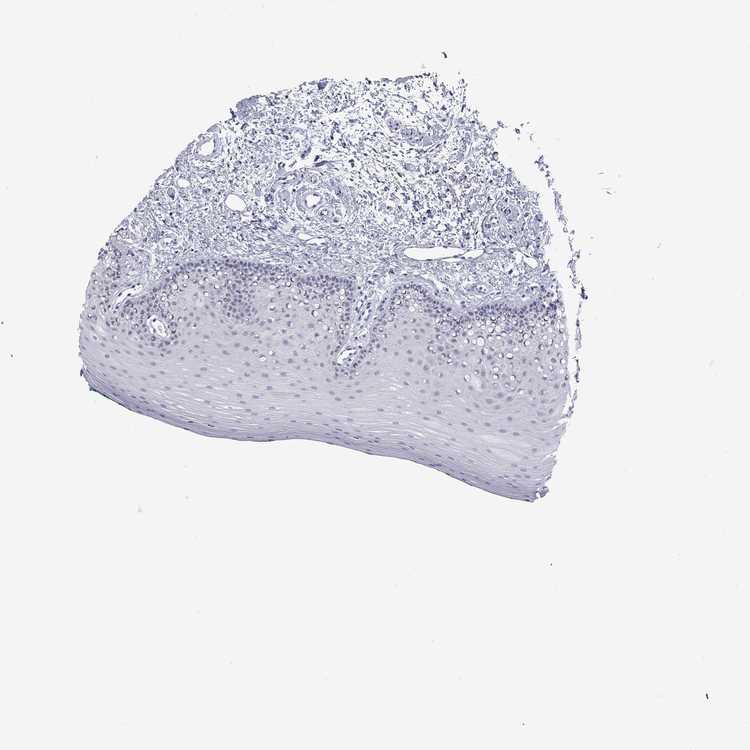

TISSUE PRIMARY DATA ORAL MUCOSA Show tissue menu

Oral mucosa

ORAL MUCOSA - Antibody stainingi

Antibody staining in the annotated cell types in the current human tissue is reported as not detected, low, medium, or high, based on conventional immunohistochemistry profiling in selected tissues. This score is based on the combination of the staining intensity and fraction of stained cells.

Each image is clickable and will lead to virtual microscopy that enables deeper exploration of all samples and also displays staining intensity scores, fraction scores and subcellular localization as well as patient and tissue information for each sample.

Antibody HPA015994Antibody HPA070835

Squamous epithelial cells Not detectedNot detected